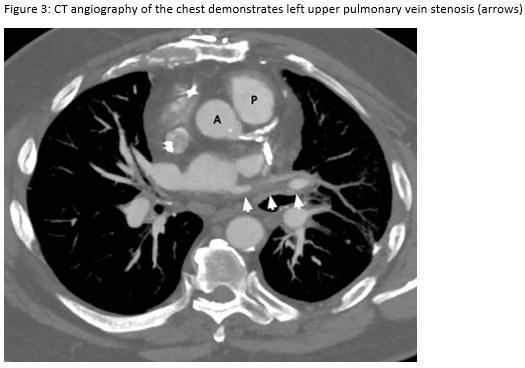

A 72-year-old man presented for evaluation of progressive dyspnea with concern for interstitial lung disease (ILD). He had an extensive cardiac history with prior cardiac bypass surgery and atrial appendage exclusion, followed by multiple subsequent radiofrequency ablations targeting arrhythmogenic foci. His last ablation procedure was three years prior to presentation. He reported reduced exertional tolerance, and was only able to ambulate a few blocks. As a part of his work-up, his local pulmonologist had obtained a high-resolution computed tomography (HRCT) of the chest, which showed abnormalities limited to the left upper lobe (Figure 1). He was treated with antibiotic therapy and corticosteroids but had no improvement so a surgical lung biopsy was performed. These images and biopsies were reviewed at our institution. A representative picture of histology from the biopsy is shown in Figure 2. After his visit to the ILD clinic, a CT angiogram of the chest was obtained and is shown in Figure 3.